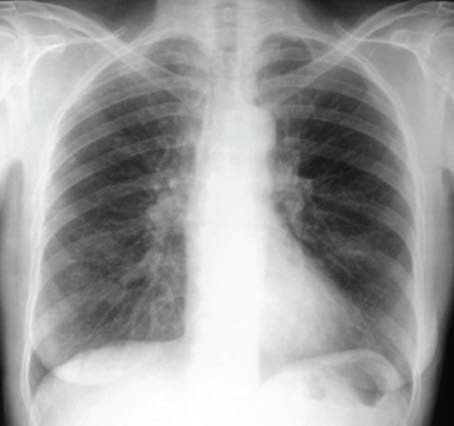

Voici l’électrocardiogramme. et la radiographie pulmonaire.

Voici la radiographie pulmonaire réalisée à l’entrée.